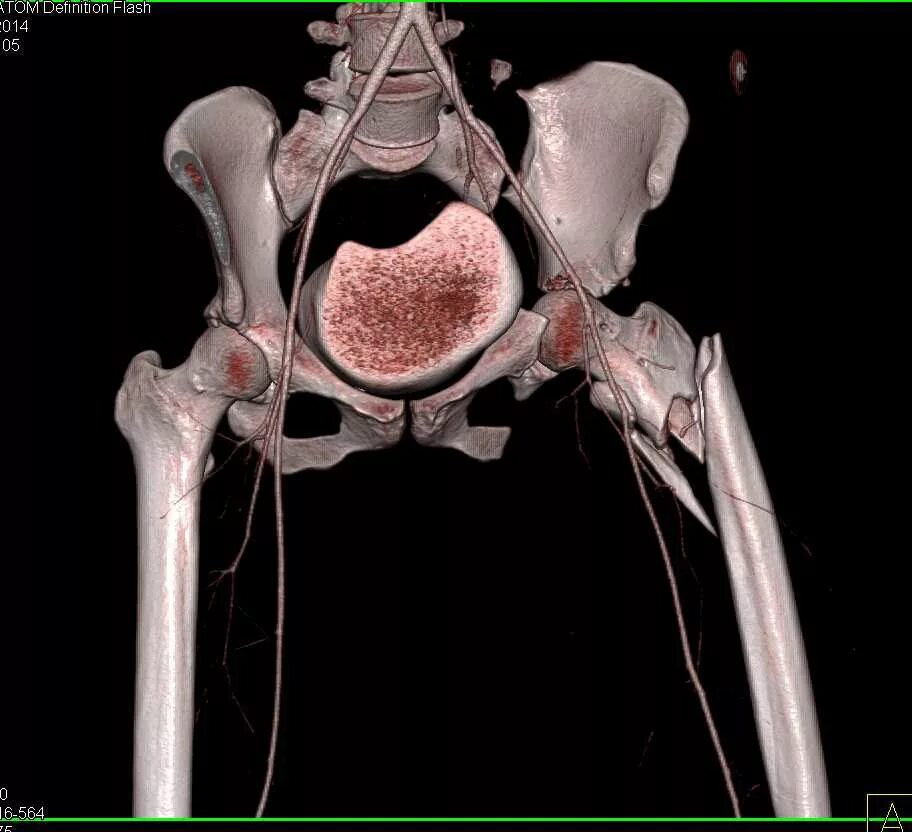

Мрт пояснично крестцового отдела тазобедренные суставы